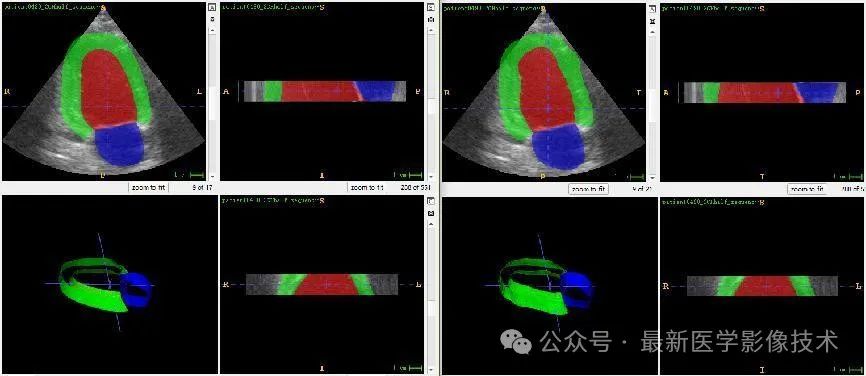

任务二、超声心动图3d结构分割

1、将图像缩放到固定大小512x512x48。图像预处理,再采用均值为0,方差为1的方式进行归一化处理,再将数据分成训练集和验证集,并对训练数据进行数据增强扩增5倍。

2、搭建VNet3d网络,使用AdamW优化器,学习率是0.001,batchsize是1,epoch是300,损失函数采用多类别的dice和交叉熵。

3、训练结果和验证结果

4、验证集部分分割结果

左边是金标准结果,右边是预测结果。